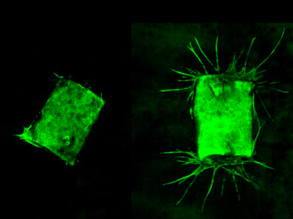

Lab Livers